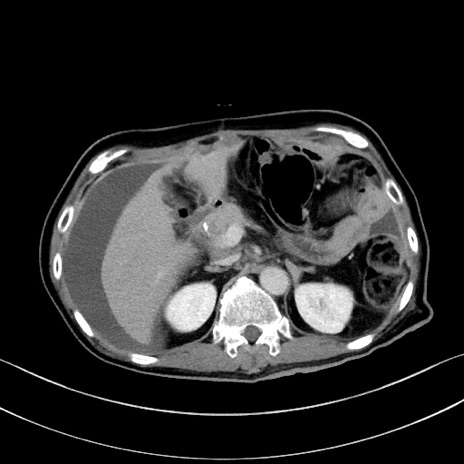

症例28(横断像)

【症例】60歳代男性

【主訴】嘔吐

【現病歴】胃癌にて胃全摘後。食思不振が悪化し、夜中に嘔吐することがある。

【既往歴】胃癌、胃全摘、脾摘、胆摘後

【データ】WBC 5900、CRP 10.56